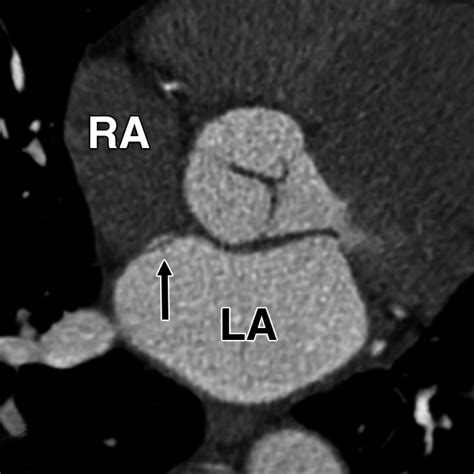

ajronline.org

ECG-Gated Cardiac CT Angiography Using 64-MDCT for …

1800×1800

ECG-Gated Cardiac CT Angiography Using 64-MDC…